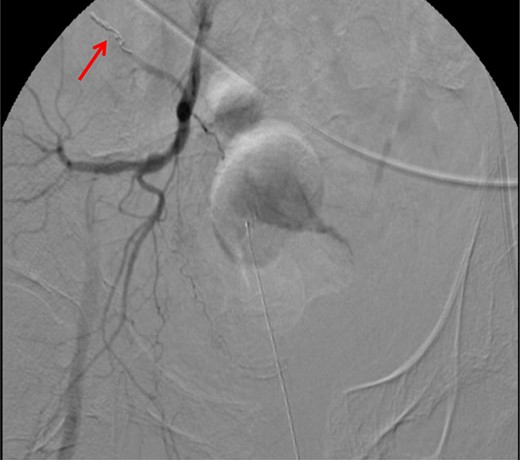

CT abdomen/pelvis with contrast was performed and a blush of contrast was noted posterior to the right pubic bone. Prior to taking patient for exploratory surgery, he was transferred to the interventional radiology suite where a pelvic angiogram was performed revealing an abnormal blush localized to the distal branches of the right iliolumbar artery (Fig. 2). Delayed phase of the angiogram demonstrated early venous filling consistent with a traumatic arteriovenous fistula which was embolized with 300–500 µ of embospheres and three 3 × 2 microcoils (Figs 3 and 4).

CT angiogram demonstrating successful embolization of AV fistula.

After resolution of the traumatic arteriovenous fistula (Fig. 2), a second blush from the right distal internal pudendal artery was identified and successfully treated with Gelfoam slurry. Subsequently, patient underwent exploratory laparotomy which revealed mesenteric and retroperitoneal hematomas. He also underwent craniotomy for evacuation of the subdural hematoma and open reduction internal fixation of the anterior and posterior pelvis. After discharge in fair condition to a subacute rehabilitation facility, patient developed a deep venous thrombosis managed by Coumadin.